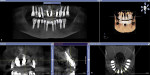

A 49-year-old nonsmoking male presented for treatment of his advanced tooth loss, terminal dentition, residual infection after dental treatment, and recurrent sinus infections. His dental history consisted of multiple attempts at conventional treatment approaches to prolong tooth longevity, several implant procedures to replace failing endodontically treated teeth and edentulous sites (all resulting in repeated failure of treatment), compromised esthetics, and various secondary infectious diseases related to previous failures of dental treatment. The pretreatment CT scan view of the maxillae and several serial views (Figure 20) demonstrated multiple edentulous sites, residual sinus infections, failing implant procedures with large alveolar defects, and the remaining dentition, which can be classified as a “terminal dentition.” After reviewing multiple treatment options with the patient ranging from conventional fixed and removable options, to partial implant reconstruction with extensive bone replacement procedures recommended, the patient opted for removal of most of the remaining dentition, correction of sinus pathology, multiple implant placement, and immediate provisionalization procedures, most accomplished by a conservative, minimally invasive protocol (except for the sinus regions, which required flap access and a lateral-wall osteotomy), and immediate loading of the implants at the initial and only surgical procedure planned. After extensive medical and dental histories were taken, medical clearance for the preexisting sinus infections was obtained, and a complete dental workup consisting of a facebow transfer, mounted maxillary and mandibular pretreatment models, a complete diagnostic waxup of both the hard and soft tissues required to be replaced, and construction of the TempStent II surgical guide and provisionalization system, the patient was given an appointment for the complex surgical visit. During this surgery, remaining dentition and implants were removed, ten implants in the maxillary arch were inserted, and bilateral sinus elevations and alveolar reconstruction was performed along with peri-implant bone grafting and immediate provisionalization. In the mandibular arch, removal of the remaining dentition was done, except for teeth Nos. 21, 22, 27, and 28, and six implants were placed and immediately provisionalized, keeping the patient in the planned first-molar occlusion scheme. The immediate post-treatment panoramic view can be seen in Figure 21. After an uneventful healing for 4.5 months, the patient then initiated the final reconstructive phase of his treatment. A 7-year post-treatment clinical view can be seen in Figure 22, with the 7-year post-treatment CT panoramic scan, axial and serial views of the maxillary central incisor seen in Figure 23.